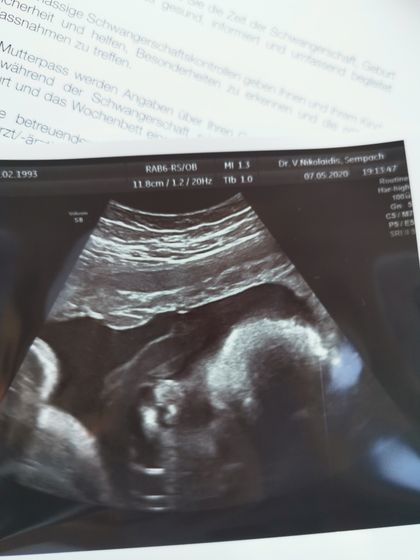

Вчера было ровно 35 недель, аж не верится ?. В эту беременность время летит очень быстро. 3 дня назад были на плановом приеме у гини. Посмотрели нашего сладкого мальчика, все у него отлично. Самая главная новость ОН ПЕРЕВЕРНУЛСЯ ? как же я рада ❤️.

Вес сыночка 2700

Рост 47 см.